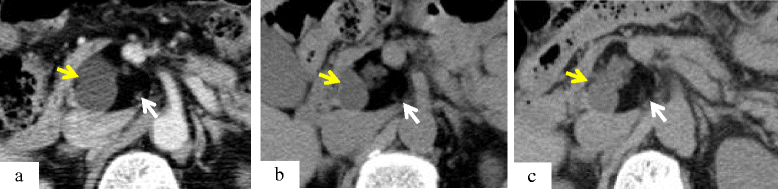

Case presentation: A 68-year-old man presented with an asymptomatic solid and multi-cystic lesion in the uncus of the pancreas, incidentally detected on abdominal enhanced computed tomography. The tumor was found to be a well-demarcated solid and multi-cystic lesion without any enhancement, measuring 4 cm in diameter. After 28 months of follow-up, the tumor enlarged. At 31 months after initial diagnosis, the patient underwent surgical resection because it was difficult to clinically determine whether the tumor was malignant or not. Macroscopically, the solid tumor consisted of yellow adipose tissue with a smooth thin capsule confined to the pancreatic uncus. The inner structure of the tumor consisted of multiple cysts with a white nodule between the cysts. Histologically, the solid part and the multi-cystic portion consisted of mature adipose tissue and colonization of dilated pancreatic ducts with mild fibrosis, respectively. Immunohistochemical findings revealed cytokeratin 7 and 19 positive staining in the epithelial cells of the ducts. Adipose tissue showed positive staining for S-100 protein and there were only a few MIB-1 positive cells. The tumor was then diagnosed as a pancreatic hamartoma.